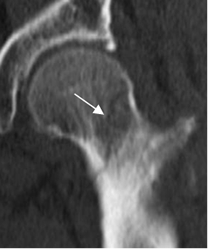

Fig 45. Fractura oculta.

TAC reconstrucción coronal. Fractura transcervical oblicua y lineal, no vista en la Rx simple. ( No mostrada).